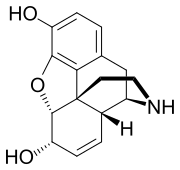

Several semi-synthetic opioids were developed in Germany in the 1910s. The first, oxymorphone, was synthesized from thebaine, an opioid alkaloid in opium poppies, in 1914.[228] Next, Martin Freund and Edmund Speyer developed oxycodone, also from thebaine, at the University of Frankfurt in 1916.[229] In 1920, hydrocodone was prepared by Carl Mannich and Helene Löwenheim, deriving it from codeine. In 1924, hydromorphone was synthesized by adding hydrogen to morphine. Etorphine was synthesized in 1960, from the oripavine in opium poppy straw. Buprenorphine was discovered in 1972.[228]